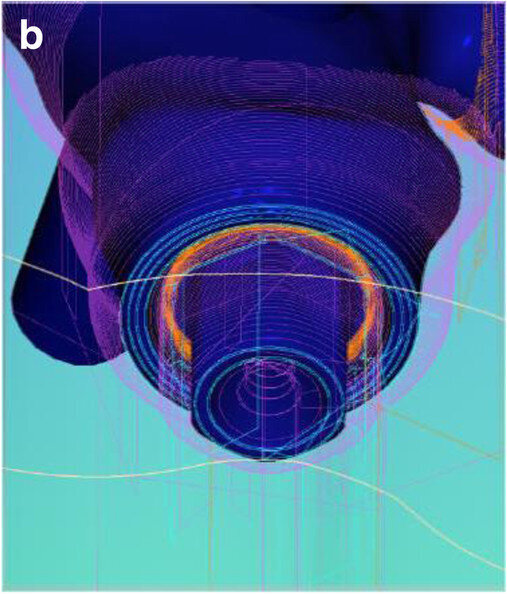

Fig. 4: Screenshot of the virtual implant planning for positions #36, 35, 33, 42 and 46, showing occlusal, sectional and panoramic views.